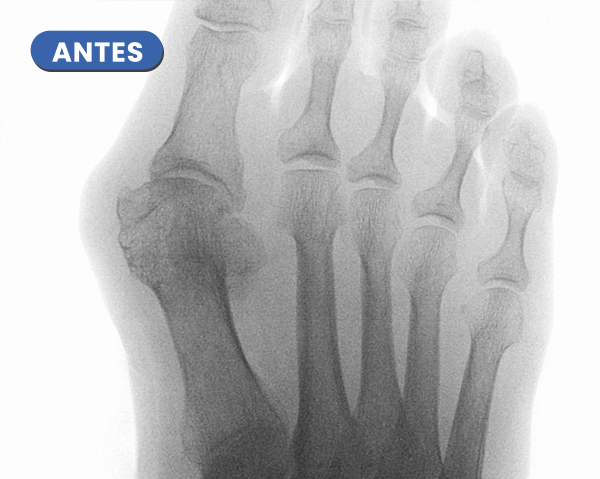

La Radiografía presenta el antes y el después a los 20 días del control radiológico tras la cura. Se aprecia la evolución en la consolidación ósea y la corrección de la articulación del hallux.